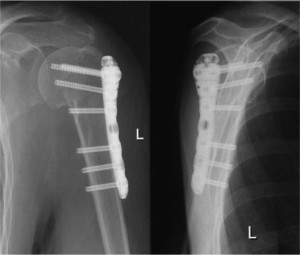

Открытое совмещение имеет важное преимущество. В отличие от следующего метода можно поставить фиксатор из металла. Это называется остеосинтезом. Для его выполнения может использоваться много устройств, например, винты, спицы и так далее.

Конечно, недостатки есть у каждого метода лечения. При использовании остеосинтеза металл проникает прямо в кость, поэтому может случиться заражение, что приводит к развитию остеомиелита. Все же преимущества более существенные, тем более их гораздо больше. Среди них:

- уверенная фиксация,

- пациент может ходить чрез три дня после операции,

- фиксация костных отломков удерживается в течение тридцати дней, пока не произойдет полная консолидация, поэтому пациент может жить нормальной жизнью.